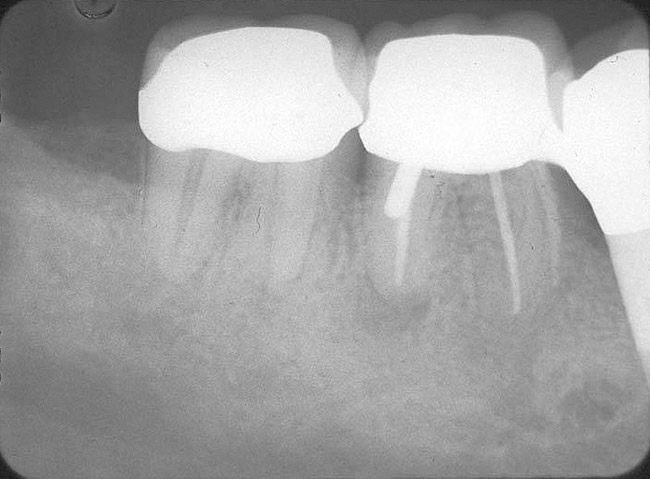

3. Extraction of a hopeless mandibular molar, defect debridement, and placement of an implant in one of the root sockets, followed by restoration with a molar-sized crown. This approach addresses the concern of two implants being placed closely together in the root extraction sockets. However, this treatment appropriately results in a mesial cantilever of the implant restoration and an area of potential plaque accumulation (Figure 1).

Implant placement at the time of mandibular molar extraction should never be attempted if there is any doubt about the ability to place an ideal dimension implant in the appropriate restorative position and attain primary stability. In such a situation it is better to first perform regenerative therapy at the time of tooth removal and place the implant in a subsequent surgical session (Figure 2 through Figure 4).